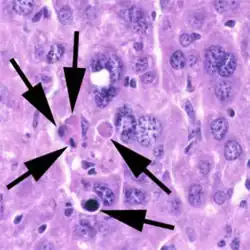

A cell undergoing apoptosis shows a series of characteristic morphological changes. Early alterations include:

- Cell shrinkage and rounding occur because of the retraction of lamellipodia and the breakdown of the proteinaceous cytoskeleton by caspases.[57]

- The cytoplasm appears dense, and the organelles appear tightly packed.

- Chromatin undergoes condensation into compact patches against the nuclear envelope (also known as the perinuclear envelope) in a process known as pyknosis, a hallmark of apoptosis.[58][59]

- The nuclear envelope becomes discontinuous and the DNA inside it is fragmented in a process referred to as karyorrhexis. The nucleus breaks into several discrete chromatin bodies or nucleosomal units due to the degradation of DNA.[60]

Apoptosis progresses quickly and its products are quickly removed, making it difficult to detect or visualize on classical histology sections. During karyorrhexis, endonuclease activation leaves short DNA fragments, regularly spaced in size. These give a characteristic "laddered" appearance on agar gel after electrophoresis.[61] Tests for DNA laddering differentiate apoptosis from ischemic or toxic cell death.[62]